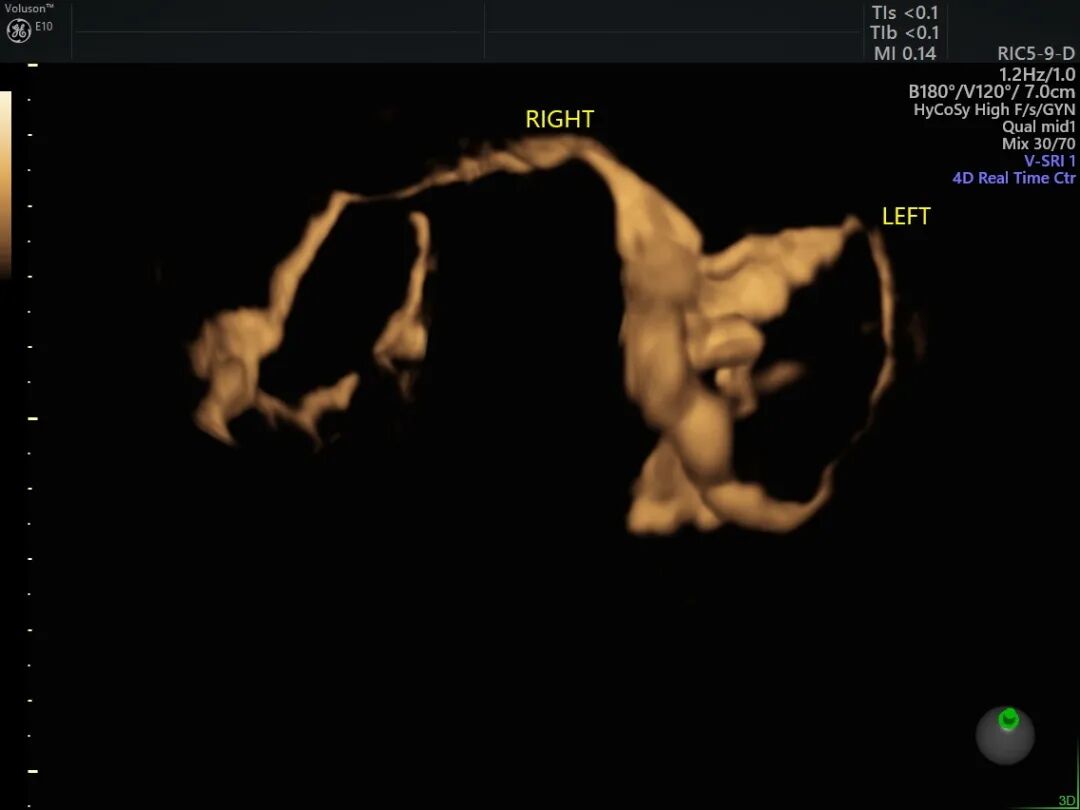

子宫输卵管造影

子宫输卵管超声造影是指向宫腔内注入造影剂,在超声下观察造影剂通过宫腔及输卵管腔时的流动情况,动态观察造影剂的弥散等情况,从而判断双侧输卵管是否通畅,输卵管的走形,子宫形态以及宫内的占位病变等。

双侧输卵管通畅